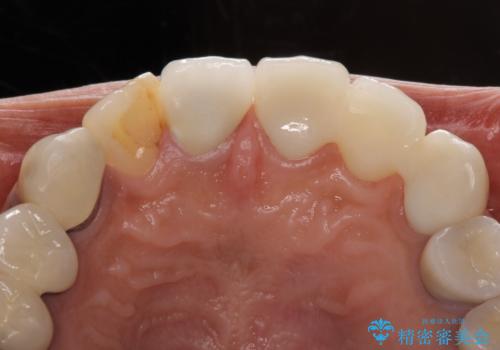

歯の裏側を一層だけ削り、接着力に頼ったブリッジを装着してはみたものの、案の定咬む力に負けて、接着が剥がれてしまっていました。

歯を削る量は増えますが、より長い期間再治療なく使用していただくことを最優先に考え、フルカバレッジのオールセラミックブリッジにて補綴することとしました。

前歯の裏側の接着面は、隙間ができていたことにより、汚れがたまるだけでなく、むし歯にもなっていました。

我々としては、治療により状態が悪化することだけは避けたいと考えているため、歯全体を覆うクラウンにすることで、より長持ちする治療を提供いたしました。